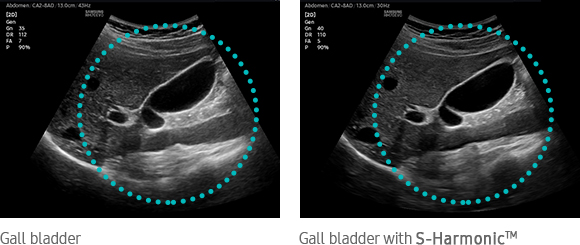

S-Harmonic mitigates the signal noise, enhances contrast, and provides uniform image performance of overall image area from near-to-far.

Gall bladder with S-HarmonicTM